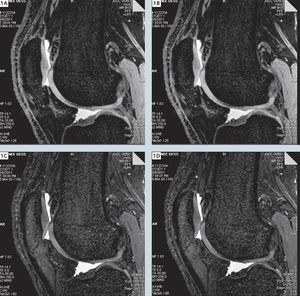

Sagittal water selective 3D DESS imaging of the knee (TR/TE 14.1/5 ms) at various flip angles (1A = 25°, 1B = 45°, 1C = 60°, 1D = 90°). With the flip angle of 60° there is highest signal intensity of synovial fluid with highest contrast-to-noise ratio of the cartilage (Thakkar et. al, 2011).